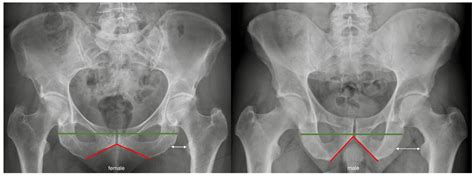

• Alignment: Proper alignment of the femoral head within the acetabulum is crucial. Misalignment can suggest dislocations, fractures, or developmental issues.

Radiologists use specific measurements and comparisons to assess the hip joint. For example, the Sharp angle and the center-edge angle are commonly used to evaluate the acetabular coverage of the femoral head. These angles help determine if the hip joint is properly aligned and functioning correctly.

• Developmental Dysplasia: This condition, often seen in infants and children, involves an improperly formed hip joint. X-rays can show shallow acetabula or dislocated femoral heads.